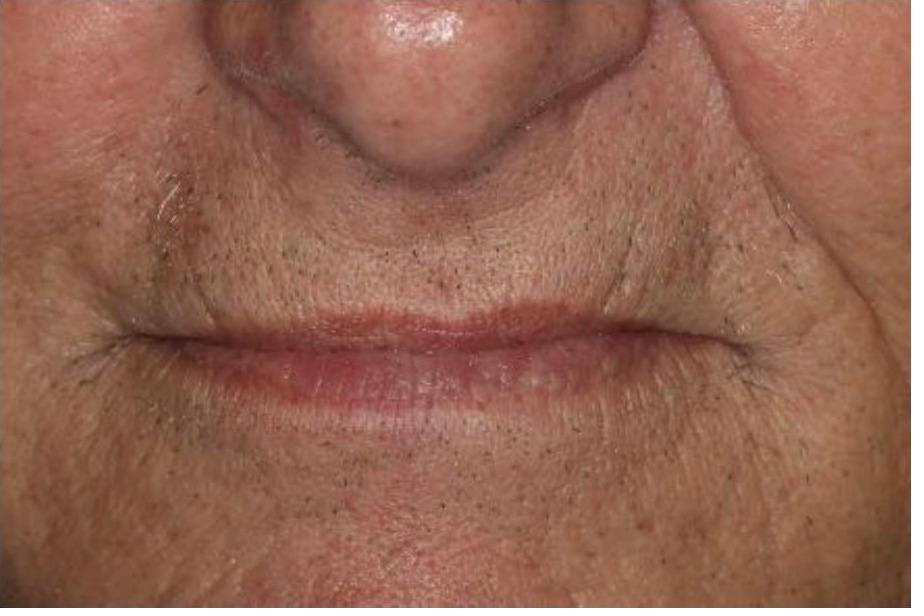

To improve this patient's dental health, esthetics and function, upper and lower implants were placed. I then fabricated an upper screw-retained implant bridge and a lower Overdenture, giving this patient back his smile and function. The patient was thrilled with the result and exclaimed "It looks good! I'll have all the women chasing me! I'd marry me if I wasn't already married!"

To improve this patient's dental health, esthetics and function, upper and lower implants were placed. I then fabricated an upper screw-retained implant bridge and a lower Overdenture, giving this patient back his smile and function. The patient was thrilled with the result and exclaimed "It looks good! I'll have all the women chasing me! I'd marry me if I wasn't already married!"

This patient was unhappy with his upper denture and lower partial denture with decayed lower teeth. Working with a periodontist and laboratory technician I fabricated a new upper denture and lower implant bridge with improved esthetics, dental health and function. He was extremely happy with the result.

This patient wanted to have his ill-fitting upper and lower dentures replaced. The back teeth were also worn, and when he smiled only the lower teeth could be seen. I fabricated new dentures for improved esthetics, fit and function, and he was thrilled with the result.

This patient was unhappy with his upper denture and lower partial denture with decayed lower teeth. Working with a periodontist and laboratory technician I fabricated a new upper denture and lower implant bridge with improved esthetics, dental health and function. He was extremely happy with the result.

This patient had an old denture that was ill-fitting and worn. I fabricated a new denture with an improved fit, function, and more youthful smile which he loved.